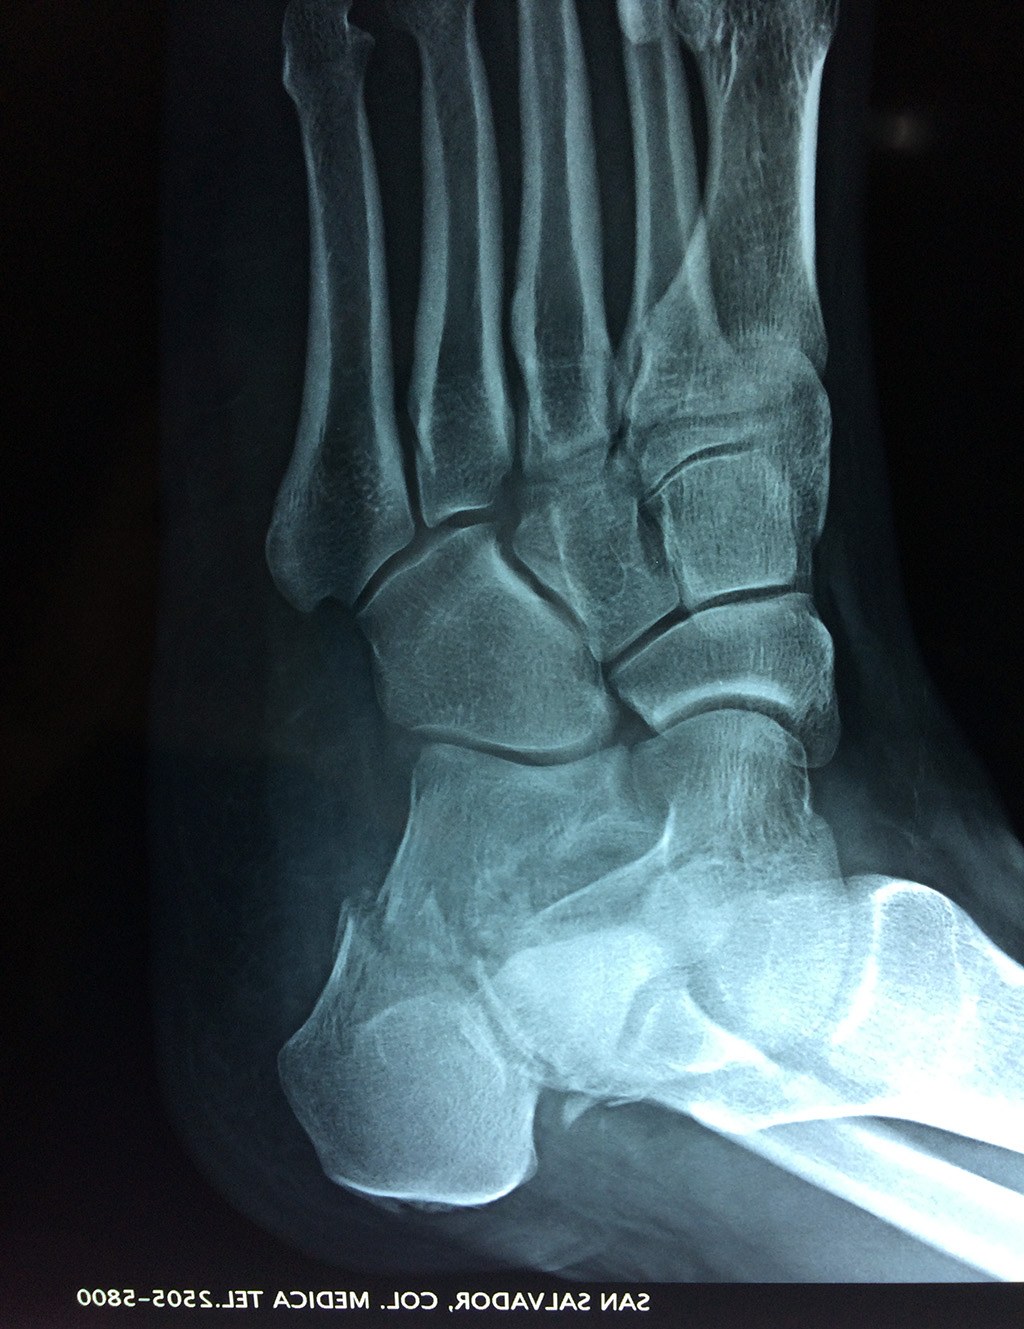

El calcáneo (del latín Os calcis) es un hueso del pie (tarso), corto, asimétrico, de forma cúbica irregular, con seis caras: superior e inferior, laterales y anterior y posterior, de las cuales dos son más o menos articulares.

Este hueso constituye el talón del pie. Se encuentra en la parte inferior de la primera fila del tarso. Se articula con el astrágalo por arriba y con el cuboides por delante. Constituye el primer punto de apoyo del pie durante la marcha, situándose en una de las zonas peor irrigadas del cuerpo y protegido plantarmente por la almohadilla plantar de tejido adiposo, con función amortiguadora.

Los retropiés varos y sobre todo, los retropiés valgos, son responsables de distintas enfermedades del aparato locomotor y contribuyen a que aparezcan alteraciones de la marcha normal fisiológica, con consecuencias clínicas importantes (dolor, sobrecargas, aplanamiento, fatiga muscular, juanetes, etc.) tanto a nivel de pie como a nivel del miembro inferior.

De todo esto se deriva que su posicionamiento espacial es muy importante para contribuir a una marcha correcta y a la salud del resto del conjunto articular del pie.